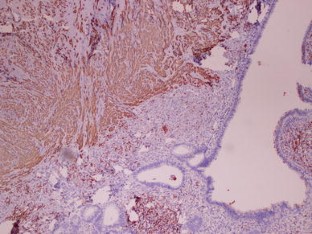

Fig. 3

• Immunuhistochemistry